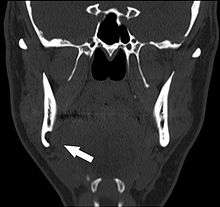

Stafne's defect is usually discovered by chance during routine dental radiography.[4] Radiographically, it is a well-circumscribed, monolocular, round, radiolucent defect, 1–3 cm in size, usually between the inferior alveolar nerve (IAN) and the inferior border of the posterior mandible between the molars and the angle of the jaw. It is one of the few radiolucent lesions that can occur below the IAN. The border is well corticated and it will have no effect on the surrounding structures. Computed tomography (CT) will show a shallow defect through the medial cortex of the mandible with a corticated rim and no soft tissue abnormalities, with the exception of a portion of the submandibular gland. Neoplasms, such as metastatic squamous cell carcinoma to the submandibular lymph nodes or a salivary gland tumour, could create a similar appearance but rarely have such well defined borders and can usually be palpated in the floor of the mouth or submandibular triangle of the neck as a hard mass. CT and clinical exam is typically sufficient to distinguish between this and a Stafne defect. The Stafne defect also tends to not increase in size or change in radiographic appearance over time (hence the term "static bone cyst"), and this can be used to help confirm the diagnosis.[4] Tissue biopsy is not usually indicated, but if carried out, the histopathologic appearance is usually normal salivary gland tissue. Sometimes attempted biopsy of Stafne defects reveals an empty cavity (possibly because the gland was displaced at the time of biopsy), or other contents such as blood vessels, fat, lymphoid or connective tissues. Defects of the anterior lingual mandible may require biopsy for correct diagnosis at this unusual location.[2] The radiolucent defect here may be superimposed on the lower anterior teeth and be mistaken for an odontogenic lesion. Sometimes the defect may interrupt the contour of the lower border of the mandible, and may be palpable. Sialography may be sometimes used to help demonstrate the salivary gland tissue within the bone.